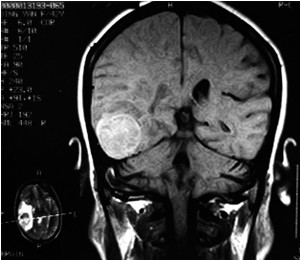

3、CT掃描:示局部有低密度區(qū)(CT值近似腦脊液密度),邊界清楚。注造影劑后無囊壁增強。本癥應(yīng)與腦穿通畸形及顱內(nèi)上皮樣或皮樣瘤鑒別。前者為腦組織缺失,腦脊液充填空腔,故腔與腦室或蛛網(wǎng)膜下腔自由交通,CT掃描可以鑒別。顱內(nèi)上皮樣或皮樣瘤在CT掃描時與本癥相同均示低密度區(qū),但其邊緣較模糊,外側(cè)壁與顱骨內(nèi)板間常有一段距離,且形狀不規(guī)則。其他尚應(yīng)與慢性硬膜下血腫或水瘤鑒別。